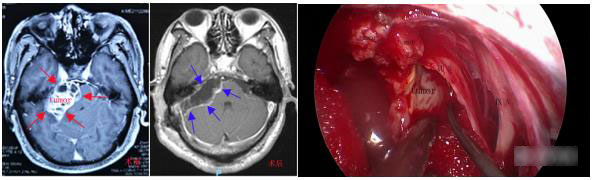

病例2:全神经内镜下经颅切除桥小脑角区巨大听神经鞘瘤